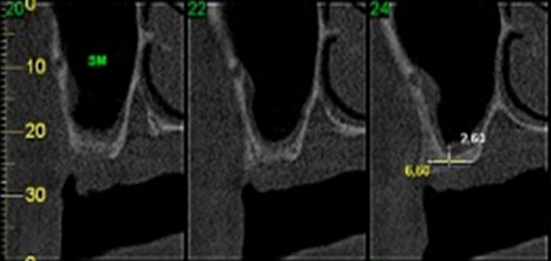

O paciente então, procurou o consultório para uma nova avaliação. Foi realizado exame clínico inicial e análise de exames radiográficos (Raio X panorâmico e tomografia computadorizada). Durante a avaliação clínica, houve extravasamento de secreção purulenta de cor amarelo citrino, e, através dos exames radiográficos pode-se constatar que um dos implantes havia rompido a parede do seio maxilar, e ali se instalado, desencadeando a infecção (Figura 2). Através dos exames radiográficos constatou-se também ausência de quantidade óssea suficiente para reabilitação do paciente por meio de novos implantes convencionais, exclusivamente (Figura 3). Além disso, verificou-se que o paciente possuía periodontite nos dentes remanescentes da mandíbula, com mobilidade de grau 3.